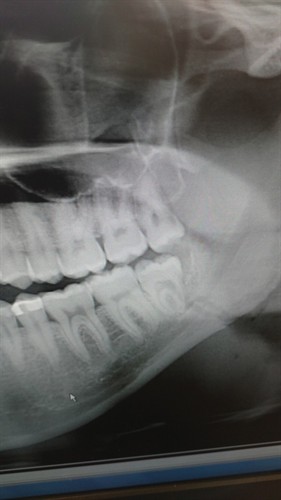

Fractured Mandible Turned into an Anatomy Review

Fractured Jaw Part 3 – What the Patient Can Do to Help

Fractured Jaw Part Two – What to Avoid